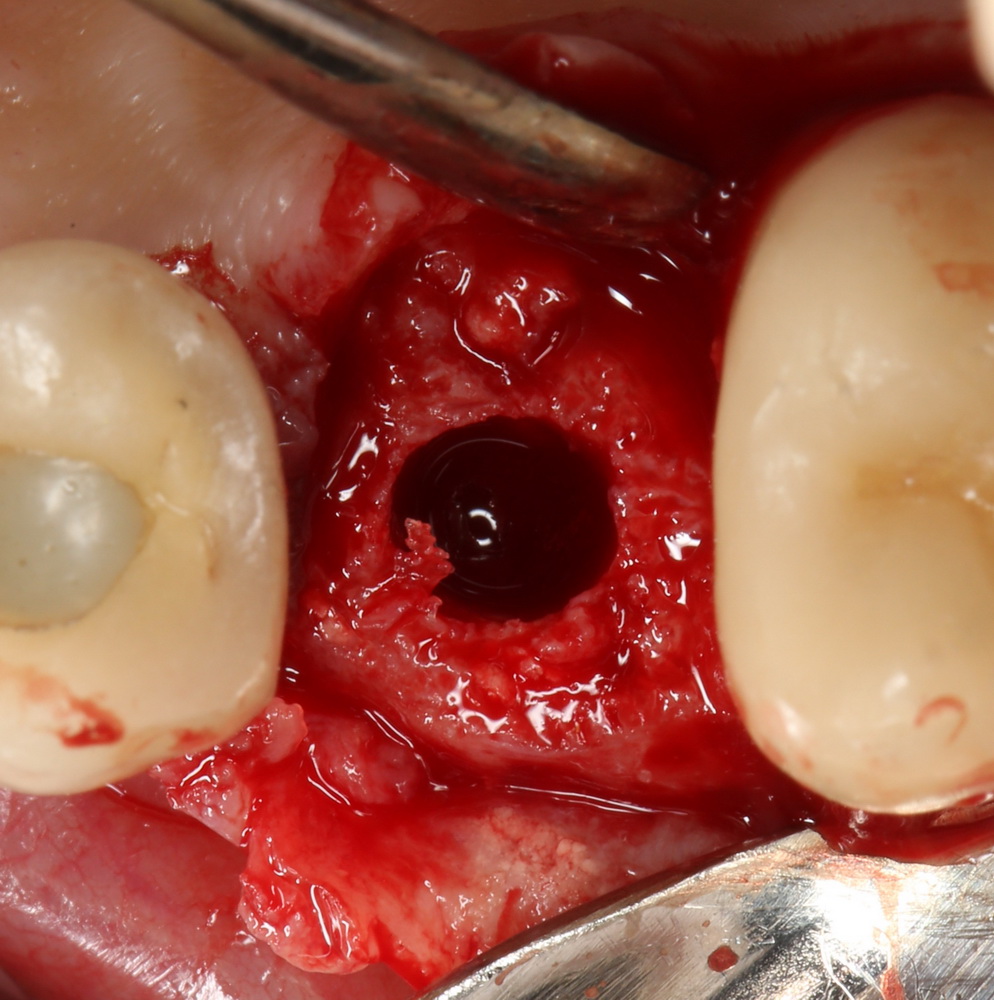

Очень аккуратно удалили зуб. Убрали из лунки все грануляции. В область верхушки корня зуба — Neocones, остальная часть альвеолы — Bioss Collagen. Сама лунка запечатывается Mucograft Seal:

Который подшивается к ее краям:

Клиническая картина в области удаленного зуба через полтора месяца:

Мечта имплантолога, не правда ли? Это я к тому, что не нужно ждать по полгода после удаления зуба — такой длительный срок ожидания приводит к сильной потере костной ткани. Не нужно превращаться в китайского пионера — самому себе создавать сложности, а потом героически их преодолевать.

Делаем разрез, скелетируем костную ткань. Вот еще один сюрприз:

Лунка зуба полностью регенерировала! Состояние костной ткани превосходное!

Это еще раз подтверждается, когда мы готовим лунку под имплантат:

Ну и, сам имплантат. Разумеется Friadent XiVE:

Еще раз напомню, что все полированные части импланта любой системы должны находиться выше уровня костной ткани. Как на фотографии.